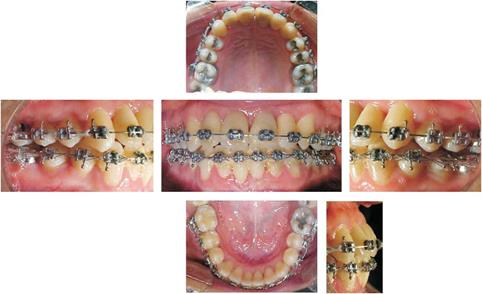

Se colocaron brackets con prescripción de Roth slot .018 x .025 en la arcada superior e inferior. Se inició la alineación con un arco 0.014 de NiTi cinchado en inferior y libre en superior para dejar que se proinclinaran los incisivos superiores aprovechando la resilencia y el módulo de elasticidad de las nuevas aleaciones que surgen de la combinación de níquel con titanio y que permite una respuesta biológica positiva del tejido periodontal.

Se continuó la secuencia de arcos al mismo tiempo que se usaban ligas de 5/16 ligeras de arriba hacia abajo a nivel de caninos y premolares para ubicar la nueva postura mandibular.

Se mantuvo la distancia entre laterales inferiores por medio de cadena elástica continua. La recolocación de brackets tuvo lugar antes de terminar la alineación y nivelación, esto es a los 8 meses después de iniciado el tratamiento. Se tomaron radiografías periapicales de control para ver los niveles de cresta ósea y el grosor óseo interradicular de los dientes anteriores para realizar un desgaste interproximal y asegurarnos de que las inclinaciones dentales adquirieran un pronóstico de salud funcional y periodontal postratamiento.

El caso fue revalorado completamente, observándose cambios positivos en las relaciones dentales, esqueletales y parodontales (nivel de crestas alveolares), por lo que se decidió hacer movimientos selectivos con cadenas elásticas continuas para obtener las clases molares y caninas adecuadas (Figura 4 y Cuadro II).

Figura 4 Etapa de revaloración. Relaciones molares en clase I, línea media centrada, clase II canina derecha 1 mm.